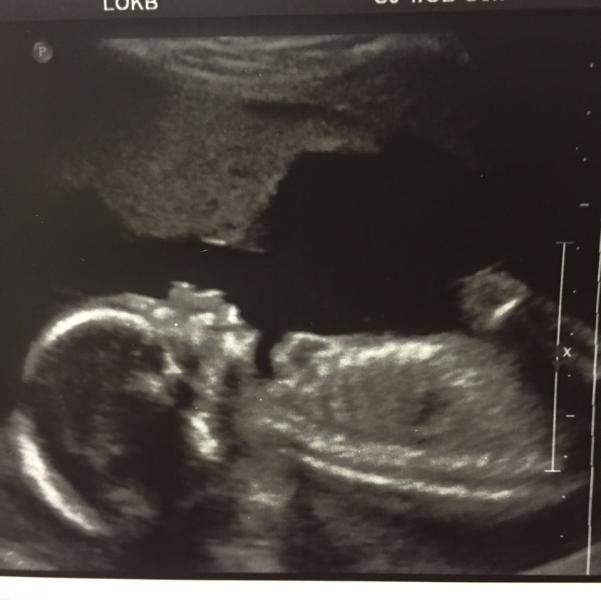

Вот и наш экватор. Сходили на 2 скрининг 😍😍😍 Предположительно мальчик стал мальчиком на 100500% (выпячил своё достоинство на пол экрана 🙈) Ходили мы как и первый раз по рекомендации моей заведующей в ЛОКБ (отделение патологии беременности) к врачу Тэн Наталье Сергеевне - врач и узист потрясающий 👍 В опытности данного врача не стоит даже сомневаться, тк я узнала если где то находят патологию в городе, отправляют к ней на консультацию и окончательный диагноз. Поэтому я спокойна на 200%. записаться...